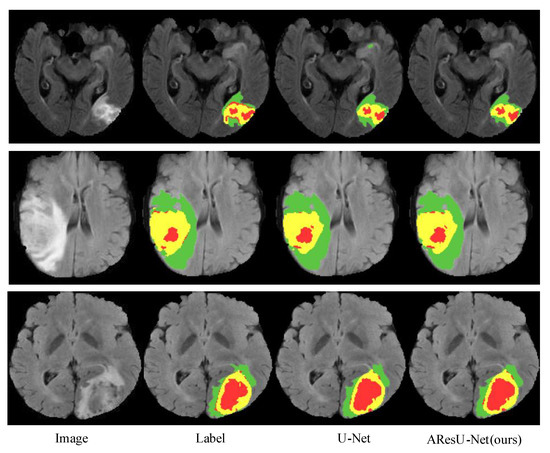

4.4. Experiment Results

4.4.1. Experiment Results on the BraTS 2017 Dataset

4.4.2. Experiment Results on the BraTS 2018 Dataset